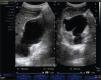

Presentación de los casosCaso 1Masculino de 12 años de edad, con antecedente de infecciones urinarias recurrentes desde los 7 meses de edad. Presenta incontinencia urinaria continua. Es manejado anteriormente con cateterismo limpio intermitente al parecer sin adecuado apego, no mostrando mejoría. Presenta una creatinina sérica de 0.7mg/dL con urea de 49mg/dL, el examen general de orina muestra: leucocituria, bacterias abundantes, nitritos positivos y proteinuria de 300 mg/dL. Presenta un cultivo positivo para Escherichia coli (E. coli) > 100,000 UFC; se indica tratamiento con antibiótico. En la cistografía se evidencia una vejiga de esfuerzo, con reflujo vesicoureteral G-5 derecho y abundante orina residual (fig. 1). El ultrasonido muestra ectasia renal derecha severa y ectasia moderada izquierda (fig. 2). La resonancia magnética de columna se encuentra normal y la valoración por Neurocirugía corrobora que no hay alteración neurológica, la cistoscopia reveló que no hay valvas uretrales. Se realiza ampliación vesical con sigmoides más estoma de Mitrofanoff, se maneja con cateterismo limpio intermitente a través del estoma. En el seguimiento presenta mejoría clínica notable a razón de cese de las infecciones, disminución de ectasia renal (fig. 3), así como desaparición del reflujo vesicoureteral (fig. 4) y continencia completa entre los cateterismos.

Caso 2Masculino de 10 años de edad, que comienza con infección de vías urinarias desde los 3 años de edad, con múltiples tratamientos antibióticos, cuenta con vesicostomía previa realizada por un tercero, presenta creatinina y urea de 1.4 mg/dL y 8mg/dL, respectivamente, ectasia renal bilateral (fig. 5) e infecciones urinarias recurrentes, motivo por el abundantes, nitritos positivos y proteinuria de 300mg/dL. Presenta un cultivo positivo para Escherichia coli (E. coli) > 100,000 UFC; se indica tratamiento con antibiótico. En la cistografía se evidencia una vejiga de esfuerzo, con reflujo vesicoureteral G-5 derecho y abundante orina residual (fig. 1). El ultrasonido muestra ectasia renal derecha severa y ectasia moderada izquierda (fig. 2). La resonancia magnética de columna se encuentra normal y la valoración por Neurocirugía corrobora que no hay alteración neurológica, la cistoscopia reveló que no hay valvas uretrales. Se realiza ampliación vesical con sigmoides más estoma de Mitrofanoff, se maneja con cateterismo limpio intermitente a través del estoma. En el seguimiento presenta mejoría clínica cual es enviado a nuestro Centro. Iniciamos manejo con antibiótico- terapia y posteriormente realizamos una cistografía que muestra reflujo vesicoureteral grado V izquierdo (fig. 6), se realizó un gammagrama renal que mostraba una disminución en la función renal total con mayor afectación del riñón izquierdo (fig. 7). La resonancia magnética de columna se encuentra normal y la valoración por Neurocirugía no evidencia problema neurológico alguno. La urodinamia realizada muestra presiones intravesicales bajas, sin contracciones no inhibidas; la cistoscopia reveló uretra permeable. Por lo tanto, se decide el cierre de vesicostomía, con reimplante ureteral izquierdo y remodelación del uréter más Mitrofanoff para el cateterismo intermitente. En el seguimiento hay una disminución importante de la dilatación en la vía urinaria superior (fig. 8) y presenta mejoría en los niveles de creatinina, así como en la función renal bilateral. Se realiza cateterización intermitente sin problema alguno.